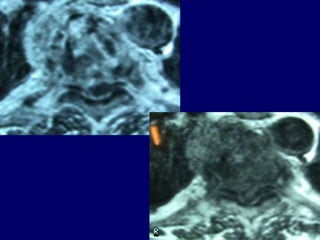

MRI